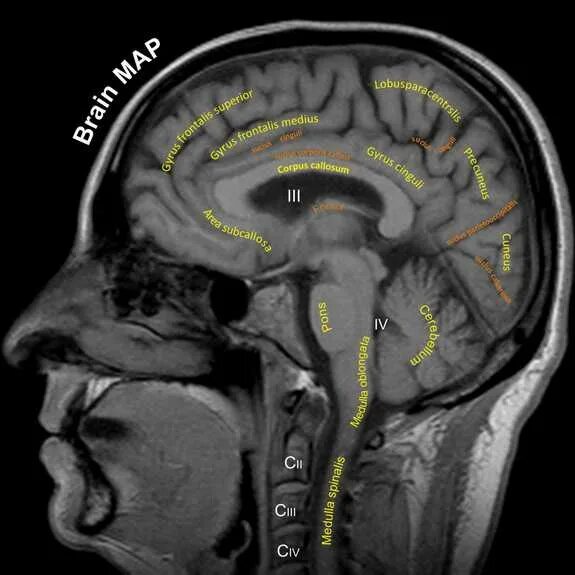

Мрт структуры